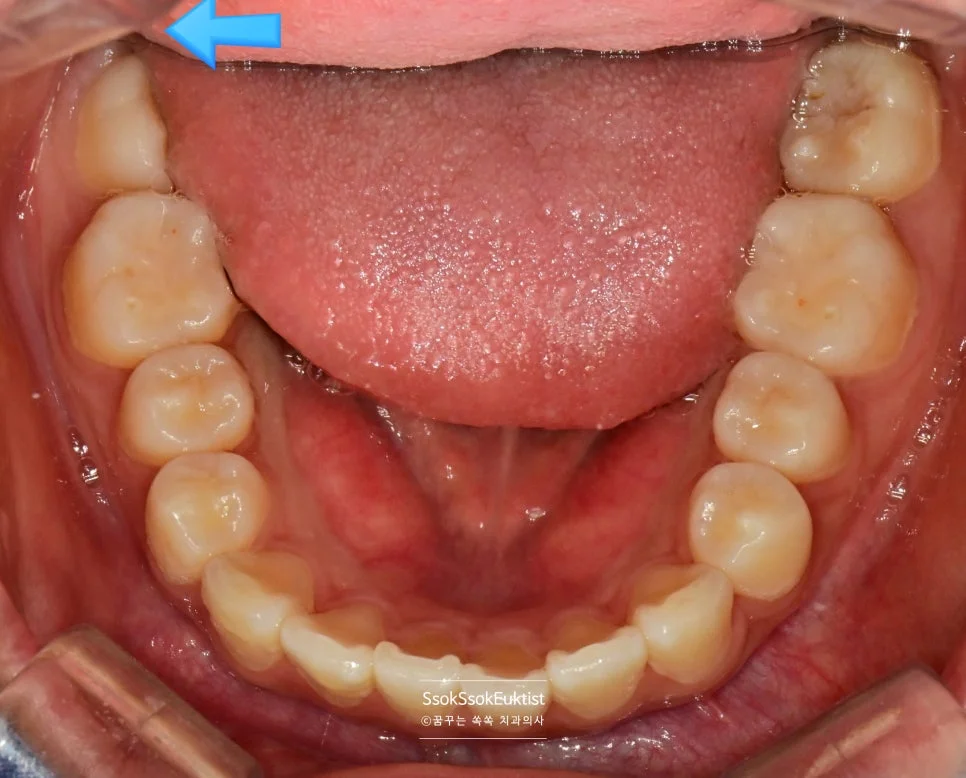

충치가 심하게 생긴 왼쪽 위아래 사랑니

충치가 심하게 생겨 사랑니 통증으로 오신 분인데요, 왼쪽 위아래 사랑니입니다.

바로 앞 치아는 멀쩡한데 왜 유독 사랑니만 충치가 있는 걸까요?

사랑니가 서로 닿아 기능하지 않기 때문입니다!

어금니의 씹는 과정(저작)은 어금니 머리를 세척, 청소하는 효과도 있는데요. 어금니가 서로 닿지 않으면 치아의 머리 면에 음식물이 계속 고여있으면서 충치가 생기게 됩니다!

예쁘게 1분 안에 발치하면 됩니다!